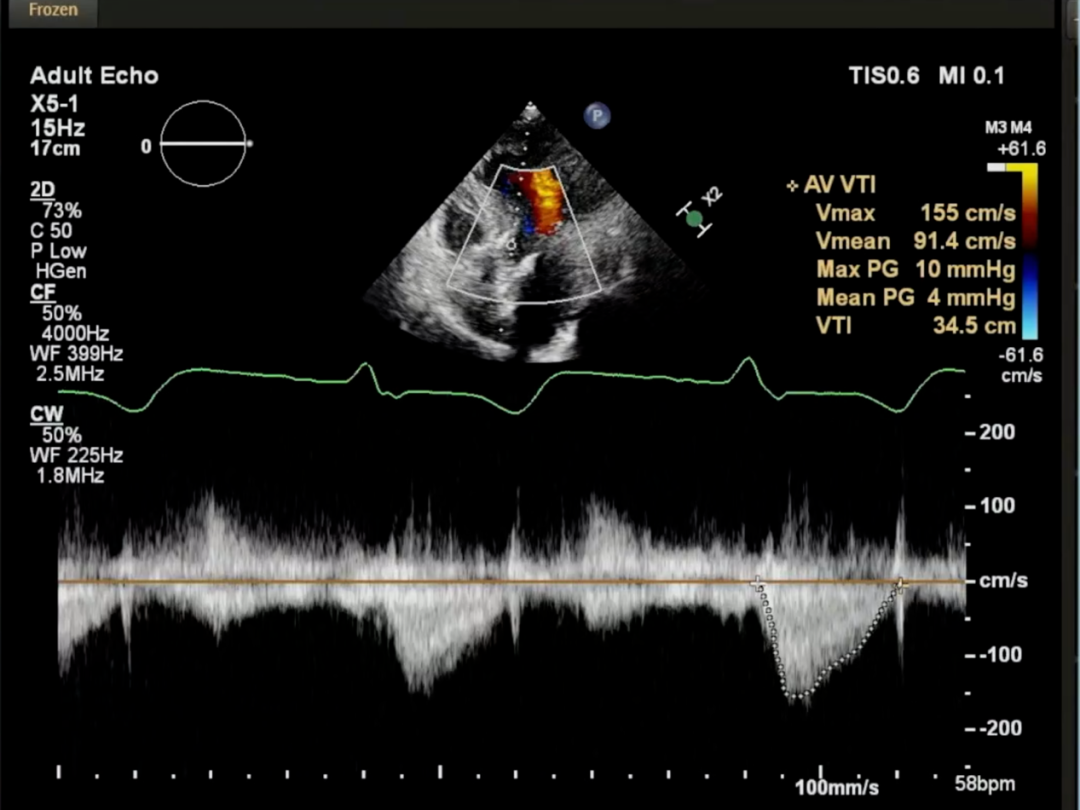

即刻超声未见瓣周漏,主动脉瓣峰值流速1.5m/s,平均压差4mmHg

最后造影亦未见反流,患者情况良好,手术顺利完成。